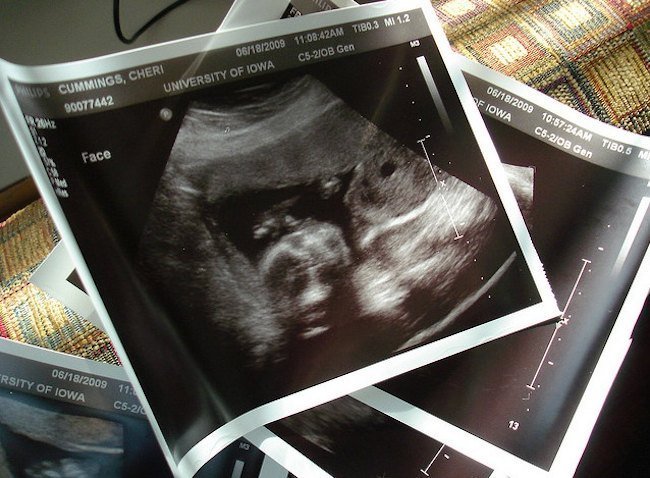

La ecografía en dos dimensiones, la más habitual (de momento) en nuestro entorno, es bidimensional y se muestra en un monitor tiempo real, aunque la imagen será borrosa si el feto se está moviendo. Por eso el doctor puede realizar varios intentos antes de captar una imagen adecuada para poder imprimir.

En el monitor las imágenes se ven en movimiento y tiempo real, pero son planas y en blanco y negro, y en la ecografía impresa en papel evidentemente también se ve imagen fija, plana y en blanco y negro.

Las ecografías en 2D son las que se realizan normalmente en la clínica u hospital para realizar un diagnóstico fetal común. Para los padres en ocasiones resulta difícil, en las fotos menos reconocibles (las que no son de la cara, manos o pies), distinguir nada en la foto tomada de una ecografía 2D.